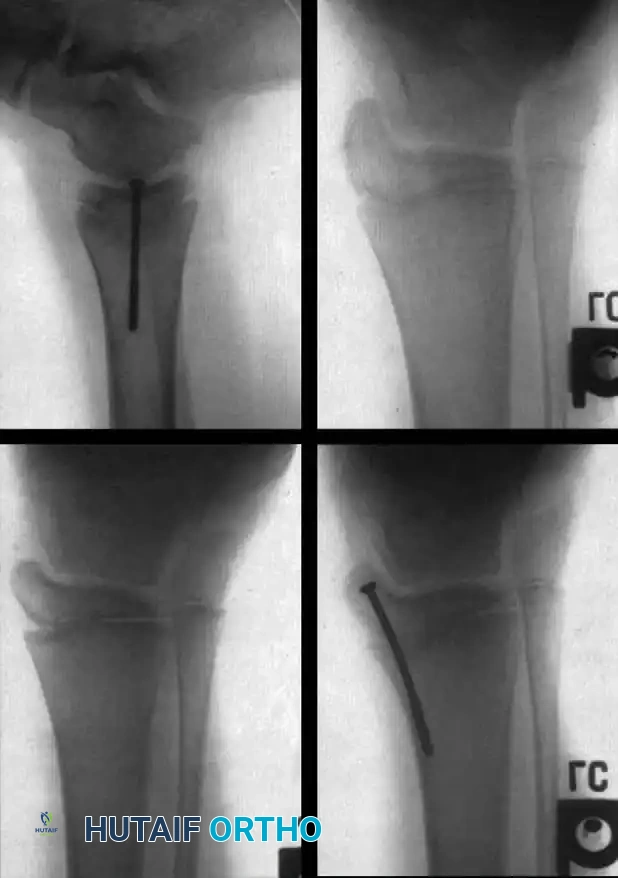

Hip Subluxation and Dislocation

Hip instability is common, particularly in L1-L3 level patients, due to the unopposed action of the iliopsoas and adductors against paralyzed abductors and extensors.

Hip Subluxation AP Pelvis

Treatment Algorithm:

* Thoracic / High Lumbar (Non-ambulators): Bilateral hip dislocations are generally left untreated. A stiff, surgically reduced hip is detrimental to wheelchair sitting. The goal is maintaining symmetric range of motion, not radiographic reduction.

* Low Lumbar (Ambulators): Unilateral or bilateral dislocations must be reduced to maintain a level pelvis and optimize gait biomechanics.

Surgical Technique (Varus Derotation Osteotomy - VDRO):

1. Soft Tissue Release: Radical release of the adductors and iliopsoas.

2. Femoral Osteotomy: A proximal femoral varus derotation osteotomy (VDRO) is performed to correct excessive femoral anteversion and coxa valga.

VDRO Preoperative Planning

1. Pelvic Osteotomy: If acetabular dysplasia is present, a Dega or Pemberton pelvic osteotomy is added to improve anterolateral coverage.

2. Open Reduction: The hip capsule is opened, the ligamentum teres excised, and the pulvinar cleared before concentric reduction.